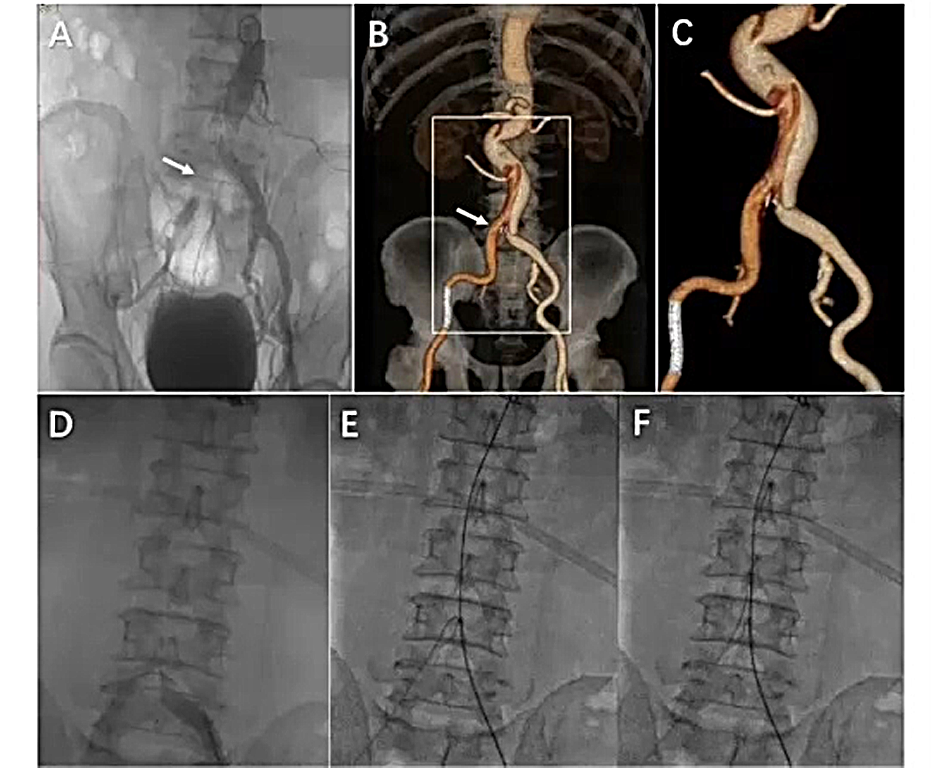

激光封堵或“剪刀技术”

通过一个病例介绍该技术的步骤:

1、使用激光导管,从下方进入假腔和真腔。(通常使用的是12F导管,长度为50cm);

2、将导丝装入导管,如下图所示推进导丝,血管造影图上可以看到导管正在向上移动。随后使用激光在行进过程中将内膜片烧毁;

3、通过下图可以看到它恢复了主动脉的正常口径,内膜片已消失,支架基本上已经打开到主动脉的真实直径,实现了远端密封。

下面术后CTA图可以看到,支架与主动脉壁完全闭合,实现了远端密封。

但是,这种技术仍然存在主动脉壁损伤的风险。导管比较短,在内脏旁的主动脉中,残留的内膜片可能会引起内脏血管闭塞,还有所谓的“苹果核”问题非常棘手,即可能有组织卡在导管内,必须格外小心远端栓塞的发生。